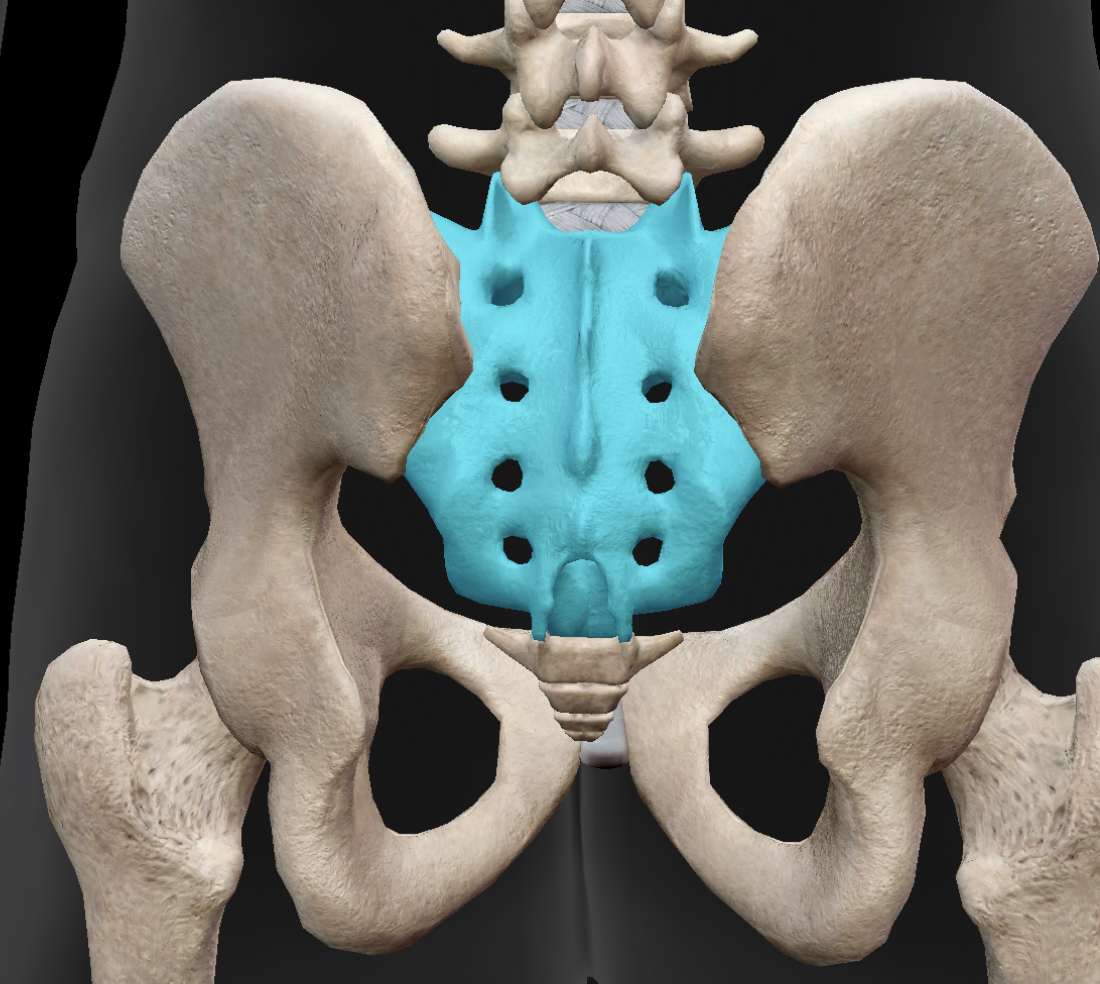

大腿二頭筋は太ももの後ろ側、ハムストリング筋と呼ばれる筋肉の一つです。骨盤を後傾させる動きや、例えばボールを蹴るような動作をするとき(股関節から太ももを後ろに引いたり膝関節を後ろに蹴り上げたり)などの動きの時に使っています。サッカーをするときはよく使ってますよね!

大腿二頭筋という名の通りこの筋肉は長頭と短頭という二つの起始部を持っています。長頭が表層にあって坐骨結節に、短頭は深層にあって大腿骨にくっついています。

ここで注目してほしいのは特に表層にある大腿二頭筋の長頭が硬くなった場合です。この長頭は坐骨結節にくっついていましたよね?この長頭は骨盤を後傾させる働きを持っているので硬く縮んでしまうと骨盤が後傾した状態が続きます。

骨盤が後ろに傾く→骨格的に股関節が外側に開きやすくなる→股関節を外に開く働きを持つ筋肉であるお尻の筋肉たちが硬くなる

というようなことが起こり、お尻の筋肉、特に梨状筋などが硬くなると坐骨神経などの神経を圧迫して腰痛を引き起こすわけです。